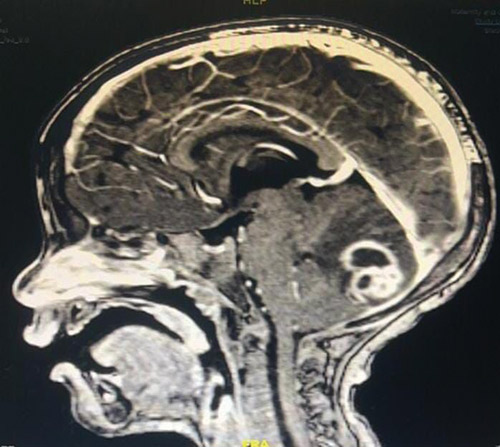

وأوضح الفريق الطبي أن الطفل كان يعاني من صداع مع خروج صديد من مؤخرة الرأس إضافة إلى إنخفاض في درجة وعي الطفل، حيث تبيّن بعد عمل «الرنين المغنطيسي» وجود زيادة في حجم الكيس الخلقي مع تجمع الصديد (خراج) في المخيخ مما أدى إلى الضغط على الأنسجة العصبية، وقد تقرّر التدخل الجراحي العاجل، حيث تم إجراء الجراحة بواسطة الميكروسكوب واستغرقت العملية 4 ساعات وتكلّلت بالنجاح ولله الحمد. وسيخضع الطفل بعد ذلك للمتابعة الدقيقة في المستشفى.